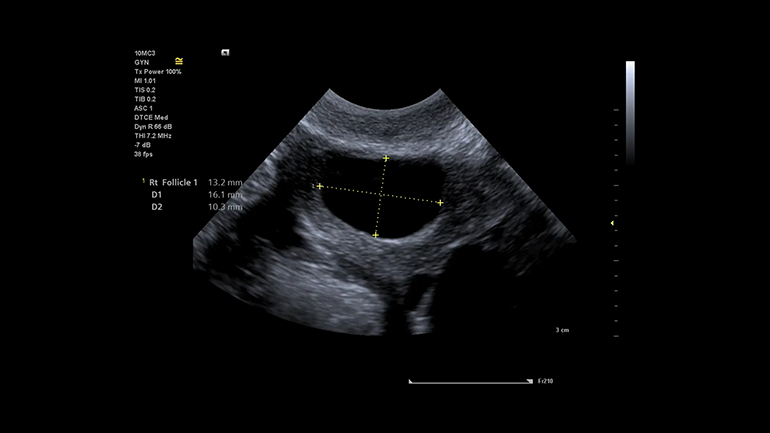

Технология выполнения измерений левых отделов сердца (eSie Left Heart). Пакет измерений левых отделов сердца eSie Left Heart — это надежный инструмент, который повышает надежность и оптимизирует рабочий процесс благодаря автоматическому определению границ левого желудочка и левого предсердия и выполнению измерений при стандартных трансторакальных исследованиях у взрослых пациентов. Технология автоматического исследования фолликулов (syngo ® Auto Follicle). В технологии syngo ® Auto Follicle реализован автоматический метод измерений, обеспечивающий быструю и точную оценку фолликулов. Автоматическое выполнение измерений и запись результатов помогают сократить продолжительность исследования.

Технология автоматического исследования фолликулов (syngo ® Auto Follicle). В технологии syngo ® Auto Follicle реализован автоматический метод измерений, обеспечивающий быструю и точную оценку фолликулов. Автоматическое выполнение измерений и запись результатов помогают сократить продолжительность исследования. Автоматизация процесса измерений (eSie Measure). Технологя eSie Measure предназначена для ускорения рабочего процесса благодаря полуавтоматическому выполнению измерений при стандартных эхокардиографических исследованиях, например. Это повышает эффективность работы и согласованность результатов для врачей-диагностов.

В гинекологии применяются специализированные программы и датчики, позволяющие качественно провести внутриполостные исследования.

Внутриполостные датчики используются в гинекологии и урологии. Бывают микроконвексные (транс)вагинальные, (транс)ректальные и универсальные (ректовагинальные) датчики. Различаются датчики, как правило, кривизной сканирующего модуля. Полостные датчики часто поставляются в комплекте с УЗИ аппаратами, предназначенными для акушерства и гинекологии.